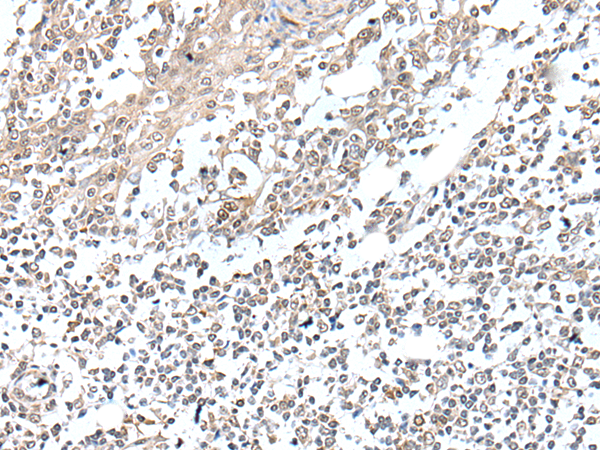

ELISA, IHC

IHC positive control:

Human colorectal cancer

IHC Recommend dilution:

25-100